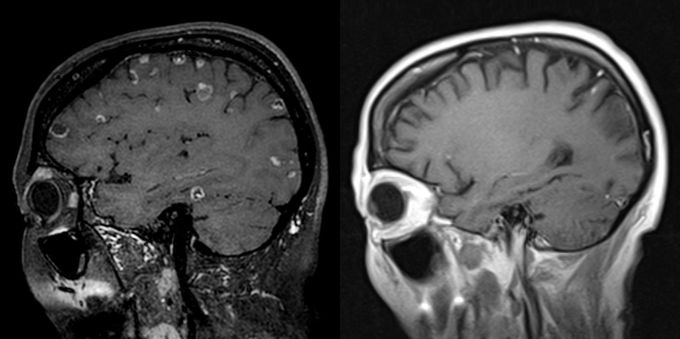

ÃÖ ±³¼ö´Â ȯÀÚÀÇ ¿©·¯ °¡Áö °Ë»ç ¿µ»óÀ» È®ÀÎÇÑ °á°ú 10¿© °³°¡ ³Ñ´Â ¾Ï µ¢¾î¸®µéÀÌ ³ú ¼Ó ±ºµ¥±ºµ¥¸¦ Â÷ÁöÇϰí ÀÖ¾î ¼­¿ï¿¡¼­ Ä¡·á¸¦ Æ÷±âÇß´Ù´Â ¸»À» ½Ç°¨ÇÒ ¼ö ÀÖ¾ú´Ù.

°á°ú´Â ³î¶ó¿ü´Ù. ¾Ï ¼¼Æ÷°¡ Ä¡·á¿¡ ¹ÝÀÀÀ» º¸À̱⠽ÃÀÛÇÏ´õ´Ï ³ú¿Í Æó¿¡ ÀÖ´ø Á¾¾çµéÀÌ ¾à 10°³¿ù¿¡ °ÉÃÄ ¸ðµÎ »ç¶óÁ³´Ù.

1°³¿ù ½ÃÇѺΠ¼±°í¸¦ ¹ÞÀº ¸»±â ¾Ï ȯÀÚ°¡ °ÅÀÇ ¿ÏÄ¡¼öÁØÀÇ ±âÀûÀÌ ÀϾ °ÍÀÌ´Ù.